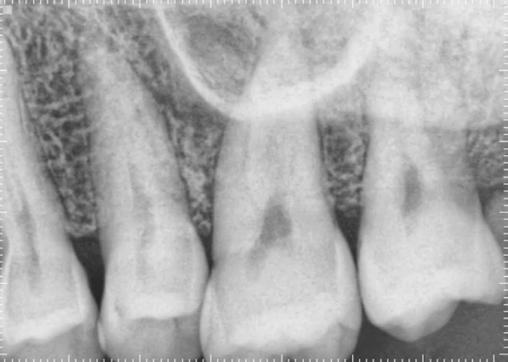

In 2016, a patient presented to my endodontic clinic for evaluation of a sore area on the palatal tissue adjacent to tooth No. 14 (Figure 5). As with every patient encounter, I performed a standard diagnostic endodontic evaluation alongside a systematic CVTE.

Clinical Findings

• Percussion: Negative

• Palpation: Positive on the palatal surface of tooth No. 14

• Periodontal Probing: Within normal limits

• Mobility: Within normal limits

• Pulpal Sensitivity (Cold): Normal response

These results pointed toward an endodontic diagnosis for tooth No. 14 of normal pulp with symptomatic apical periodontitis (due to a positive finding of palpation on the palate). But what caught my attention was not the tooth — it was the tissue.

During the CVTE, I noted a small raised swelling on the palatal surface (Figure 6) and a separate white nodular lesion on the buccal gingiva adjacent to tooth No. 14 (Figure 7). Importantly, these findings did not align with any odontogenic pathology typically associated with tooth No. 14. That clinical inconsistency provided the moment to pause and widen the diagnostic lens.

This patient was compliant and presented to the OMS the next day. The OMS performed their own examination and determined that a biopsy was necessary. The biopsy results revealed:

“Diffuse large B-cell lymphoma of the left maxillary sinus, germinal center phenotype” (Figure 8).

Figure 5: Radiograph